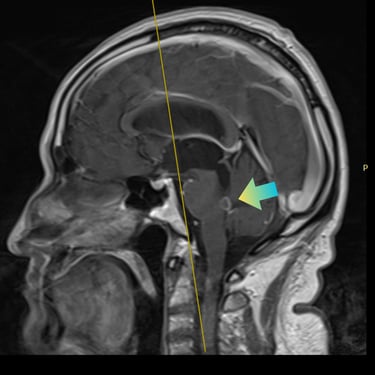

La hidrocefalia es una condición caracterizada por la acumulación anormal de líquido cefalorraquídeo en los ventrículos cerebrales, lo que genera aumento de la presión intracraneal y síntomas como cefalea, náuseas, alteraciones cognitivas y trastornos de la marcha. Cuando el manejo médico no es suficiente, la derivación ventriculoperitoneal (DVP) es el tratamiento quirúrgico más utilizado. Este procedimiento permite drenar el exceso de líquido desde el cerebro hacia la cavidad abdominal, donde es reabsorbido, aliviando la presión intracraneal y mejorando la función neurológica. El tratamiento oportuno es clave para prevenir secuelas.